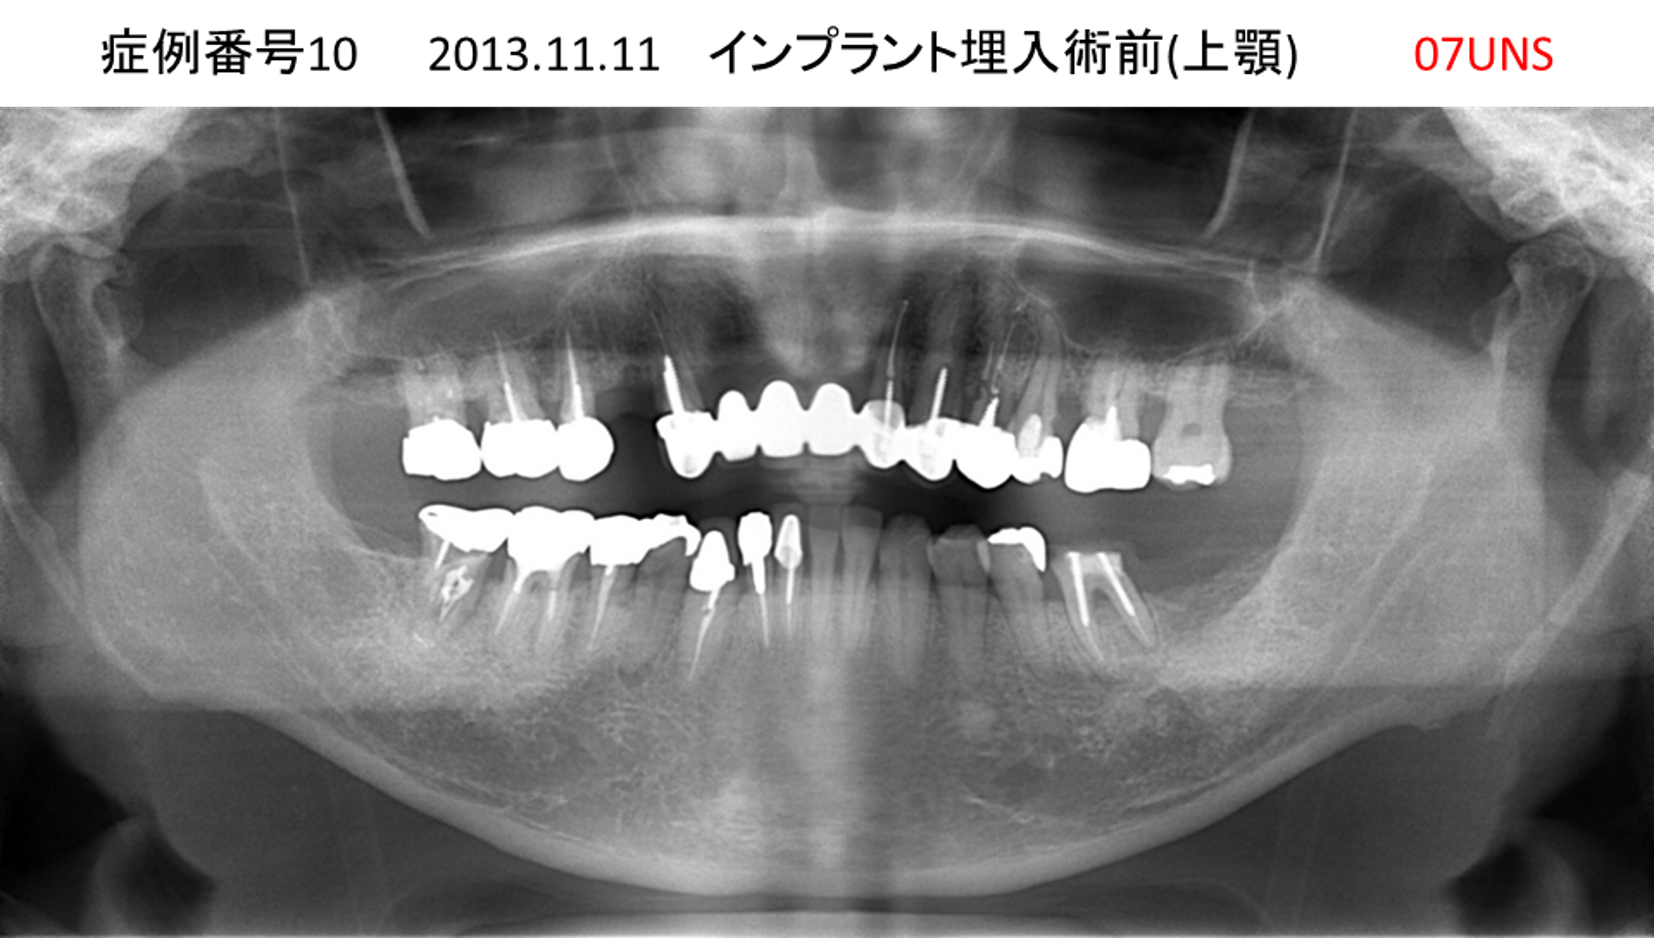

上の前歯が揺れてきてかめない患者様のインプラント症例

| 治療名称 |

インプラント |

| 治療費用 |

440万円+税 |

| 治療期間 |

6か月 |

| 患者さんの症状(主訴) |

上の前歯が揺れてきた。かめない |

| 治療内容 |

サイナスリフト、GBR、インプラント、即時荷重 |

| 治療結果 |

上の前歯の揺れが収まった。奥歯でしっかり噛める。 |

| 治療の注意点(リスク/副作用) |

インプラントが壊れたら再治療が必要 |